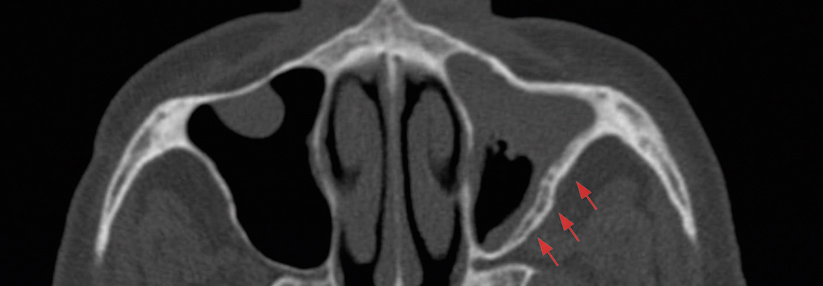

Ob sie eine Reise trotzdem wagen dürfen, hängt vor allem von Art und Zeitpunkt des Eingriffs ab. HNO-Patienten haben zum Beispiel am ehesten mit den speziellen Druckverhältnissen in der Luft zu kämpfen. Der Druck im…